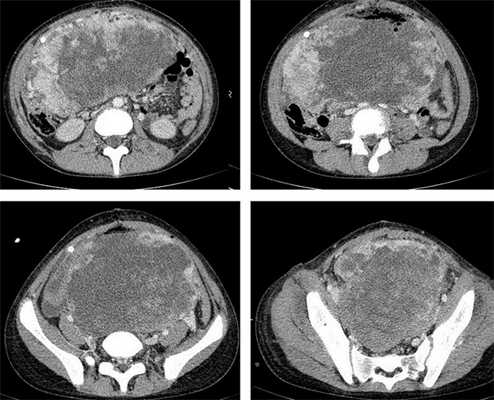

Компьютерная томография органов грудной клетки, брюшной полости, малого таза используются для оценки распространения опухолевого процесса (рис.5).

После получения гистологического заключения о характере опухоли, данных обследования: КТ грудной клетки, брюшной полости, КТ/МРТ малого таза, уровень опухолевых маркеров, проводится стадирование, определение прогноза, и командой специалистов принимается решение о лечебной тактике.

![КТ органов брюшной полости – опухоль яичника]()

Рисунок 8. КТ органов брюшной полости – на снимках вы можете увидеть опухоль яичника.